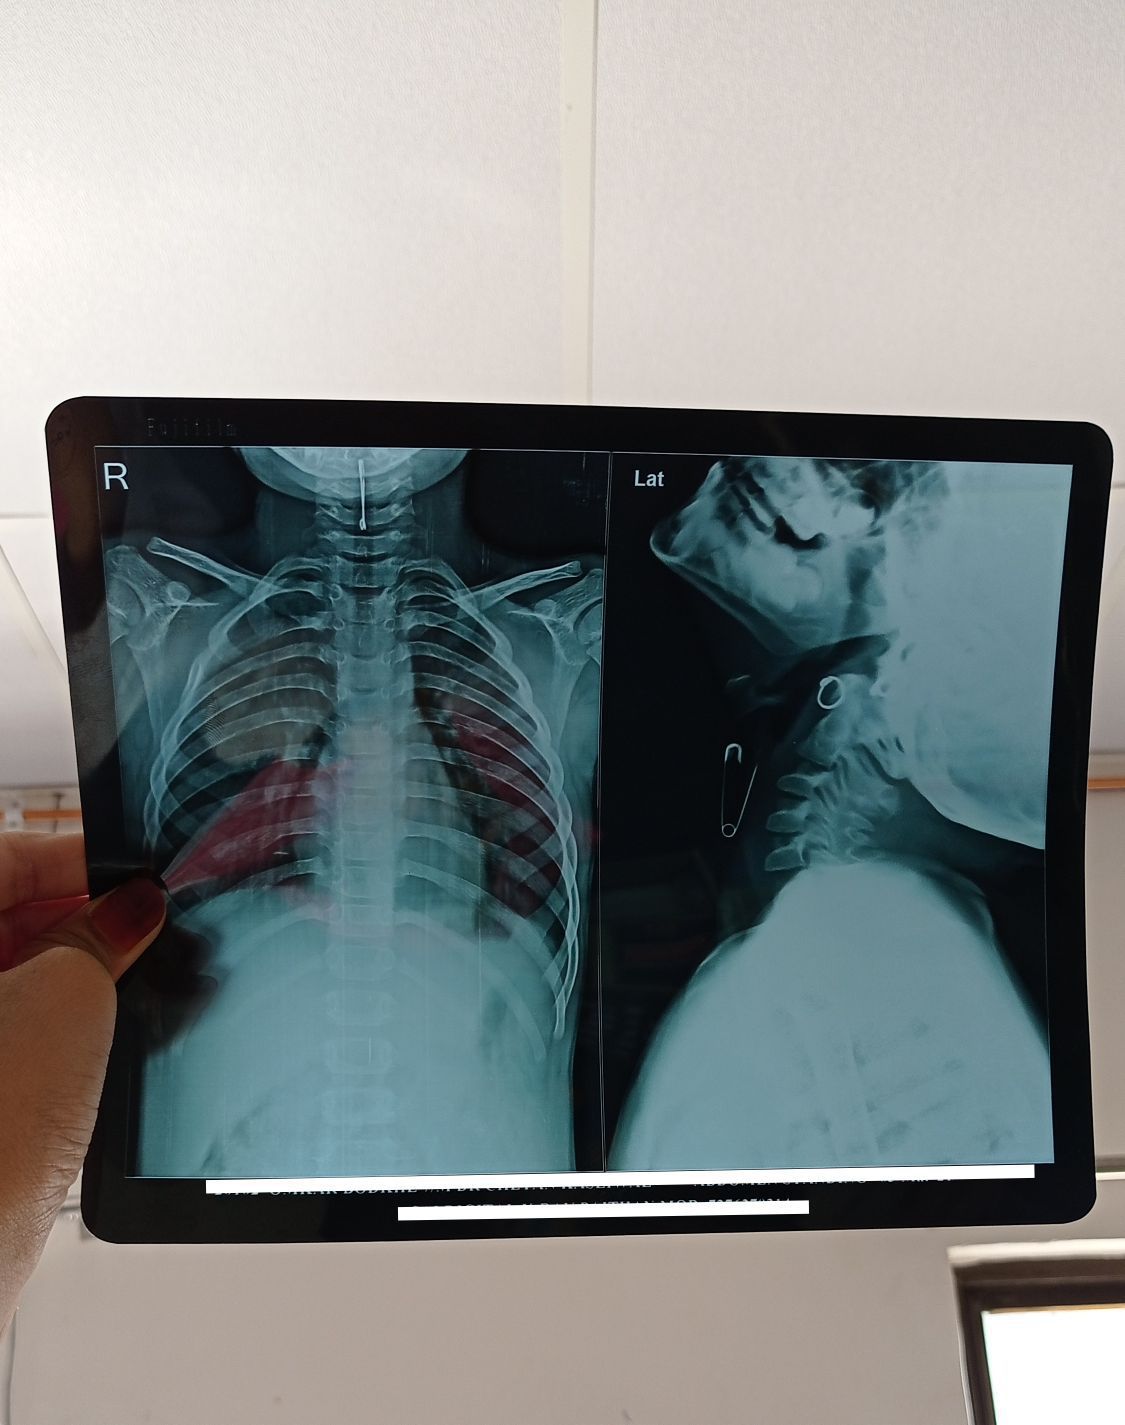

A 7 yr old boy admited at hospital. C\o:- pain in throat. Blood tinch saliva. O\E:- pin is in the upper part of trachea not in oesophagus. T\T:- pin is removed by simple procedure using tongue depressor. Prognosis:- Good. Boy is discharged within 24 hrs.

ABC's first then endoscopy discharge in day or so after educating parents on forgen body's and how to maintain a child safe environment. EMT-here